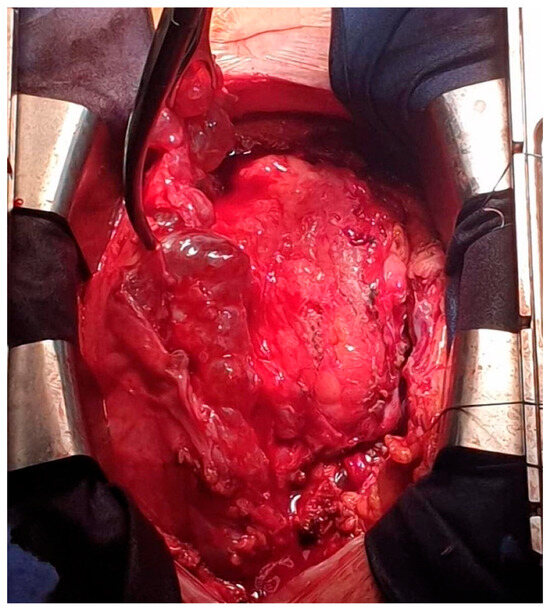

A Rare Case of Multilocular Mesothelial Inclusion Cysts of the Pericardium: Diagnosis, Treatment, Follow Up, with Comprehensive Review of the Literature

by Ali Shadmanian, Kosha Patel, Endre Alács, Henriette Gavallér, Szilva Agocs and Miklós Bitay

Background: Multilocular mesothelial inclusion cysts—also known as benign multicystic mesothelioma (BMM)—are rare, typically arising in the peritoneal cavity. Pericardial involvement is extremely uncommon and can pose diagnostic and therapeutic challenges due to their recurrent and infiltrative nature. Accurate diagnosis and surgical strategy are [...] Read more.

Background: Multilocular mesothelial inclusion cysts—also known as benign multicystic mesothelioma (BMM)—are rare, typically arising in the peritoneal cavity. Pericardial involvement is extremely uncommon and can pose diagnostic and therapeutic challenges due to their recurrent and infiltrative nature. Accurate diagnosis and surgical strategy are critical for management and recurrence prevention. Methods: We present the case of a 36-year-old woman with a prior history of malignant melanoma who developed recurrent multilocular cystic masses of the pericardium. Initial imaging with echocardiography, cardiac magnetic resonance (CMR), and computed tomography (CT) revealed multilocular pericardial cysts. Surgical resection was performed under cardiopulmonary bypass (CPB), but complete excision was limited due to epicardial infiltration. Histopathology confirmed a benign mesothelial origin. One year later, recurrence prompted a second surgical intervention with total pericardiectomy and Gore-Tex patch reconstruction. Results: Postoperative recovery was uneventful in both instances. Follow-up imaging at 6 and 12 months demonstrated no significant recurrence. Histological analysis confirmed benign cysts lined with mesothelial cells, positive for calretinin and WT-1. This represents one of the first documented living cases of pericardial BMM managed with staged surgery and total pericardiectomy. Conclusions: Pericardial BMM is a rare, benign, but potentially recurrent lesion. In cases of extensive or recurrent disease, total pericardiectomy may offer definitive treatment. Multimodal imaging, histopathological evaluation, and personalized surgical planning are essential for effective management. Full article

Show Figures

Figure 1